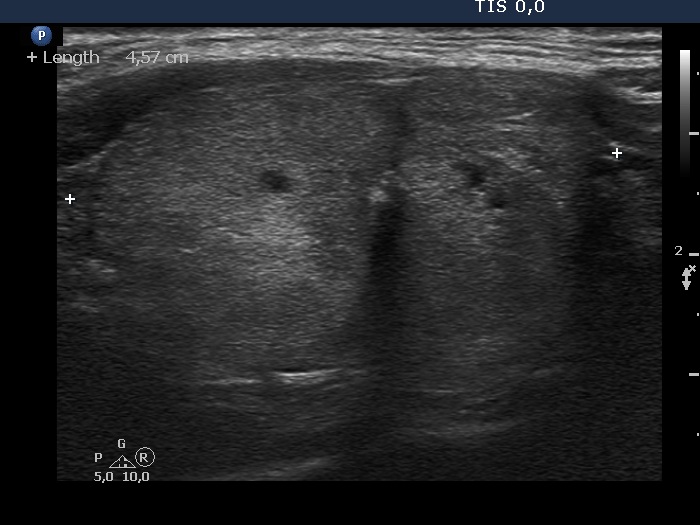

Ethanol sclerotherapy: non-toxic solid nodules - Case 5

Fourteen years after the therapy (ultrasonographic picture 6)

Middle part of the left lobe, longitudinal scan.